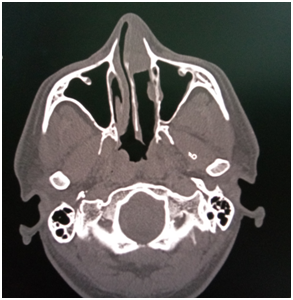

48 year old male coast guard personnel, a known case of Primary Hypertension and Type II Diabetes Mellitus, presented to this centre with Left nasal mass and bleeding from Left nostril of 04 months duration. There was history of similar complaints for the past 23 years. History of bathing in pond in his village which is in Southern part of India since his childhood. No history of rhinorrhoea /excessive sneezing/trauma to nose. Patient was diagnosed as Rhinosporidiosis and underwent excision of the mass thrice, in 1994, 2006 and 2017. On evaluation, there was a red friable mass filling Left nasal cavity, with spores seen on the surface and bleeds on touch (Figure 1). Computed Tomography of Paranasal sinuses (PNS)–shows Left nasal cavity filled with soft tissue on the anterior aspect, absent middle and inferior turbinate (Figure 2). He underwent Nasal Endoscopic Excision (Microdebrider & CO2 laser assisted)-mass was removed using Bipolar diathermy and CO2 laser, the lateral wall of the nasal cavity was drilled at basisphenoid , Agger nasi and at medial maxillary wall. CO2 Laser was used at nasal septum and nasopharynx. In our centre we are using CO2 laser especially at the areas of contact over nasal septum nasal floor & at nasopharynx. Histopathological Examination (HPE) report shows-numerous variably sized thick walled sporangia containing numerous spores, foci of ruptured sporangia also noted with spilling of spores into the adjacent stroma, with chronic inflammatory infiltrates (Figure 3). Post-operative period was uneventful; he was started on Tablet Dapsone 100 mg, 1 tab daily for 01 year.